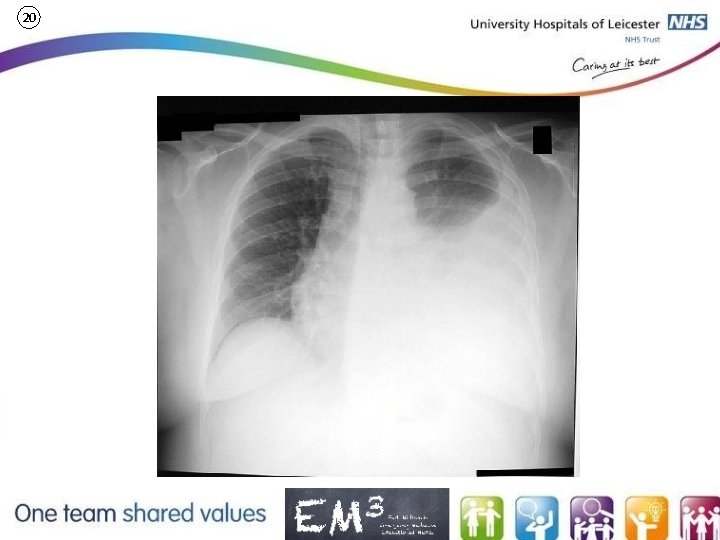

20 ED Simulator Based Training – Scenario Guide Set Adult ED Resus Room Time: (45 mins) Simulation: 30 Debrief: 10 Recover: 5 Scenario (Start) Scenario (Progression) Equipment 86 y/o fall from standing against a chest of draws. On floor for ? 24 hrs Pain in chest and leg PMH: Hypertension, Hypothyroid, IHD DHx: Aspirin, Ramipril, Bisoprolol, Thyroxine, Simvastatin SHx Lives alone ABC Sim-Man (complete kit) Recognise chest injury Lifepak defib with training leads Recognise obs may represent shock Chest Drain Training ‘resus’ equipment trolley CT full trauma series. Grey Wig Main objectives (Clinical and Educational Context): • To demonstrate effective assessment in trauma • Recognition of significant injury despite low mechanism • Identify need for chest drain and insert appropriate drain • Respond to physiology Position Alert on ED trolley in resus bay Simulator start state Physiology A – Clear & self maintaining. B - Rate 25, Sp. O 2 87%. (15 l) C - Pulse 72, BP 110/75 D – E 4 V 4 M 6 pupils equal E – Tpr 34. 9 Expected course: Recognise abnormal physiology initiate resuscitation insert chest drain stabilises CT Clinical Findings • Reduced air entry left chest • Soft abdomen • Painful hip movements • Some restriction of neck movement